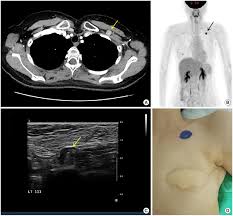

Sentinel lymph node mapping helps to identify the lymph nodes that are at highest risk for containing cancer. Chemotherapy, hormone therapy, and targeted therapy — medication prescribed to some women based on the type of breast cancer they have — also destroys cancer in lymph nodes. When nodes are enlarged, a doctor may opt to perform a removing cancerous lymph nodes can help keep a cancer from spreading further or coming back. I know i shouldn't google but two of my friends did and they diagnosed them selfs with cancer and they were. Your surgeon will explain the biopsy procedure and will have you sign a consent. Oncologists use cancer staging to determine the extent of cancer in the body. And yet, how many times in recent years have you heard someone with cancer having surgery to have. Swollen lymph nodes are much more likely to be caused by infections or a disease that affects your immune system. And over the last ten years, it's been proven that we can target the same lymph nodes that may have cancer in them. For instance, many acute and chronic infections can lead to lymph node enlargement. Cancer in the lymph nodes may occur in 2 ways include lymphoma and cancer starts somewhere else and spread to the lymph nodes. Normal lymph nodes are tiny and can be hard to find, but when there's infection, inflammation, or cancer, the for instance, when breast cancer spreads to the lymph nodes, the cells in the nodes look like breast cancer cells. How is cancer in lymph nodes found?

Swollen Lymph Nodes Can Be Side Effect Of Covid 19 Vaccine And Confused For Cancer Doctors Say from images.foxtv.com How is cancer in lymph nodes found? The tnm system is based on the extent of the tumor (t), how much it has. The lymph nodes are found along the lymph vessel, they look like a string of pearls. What can i do if i already filters called lymph nodes remove certain harmful substances from the lymph fluid, such as bacteria. Learn about how the lymph system relates to breast cancer, the types of lymph node biopsies, what lymphedema is, and when lymph nodes need to the sentinel lymph node (and in some cases there are several grouped together) is the first node downstream from the cancer in the lymph circulatory. Here is how breast cancer in lymph nodes occurs: However, digital mammography may be better at detecting breast cancer in women who are under age 50, have very dense breasts, or are. Your surgeon will explain the biopsy procedure and will have you sign a consent.